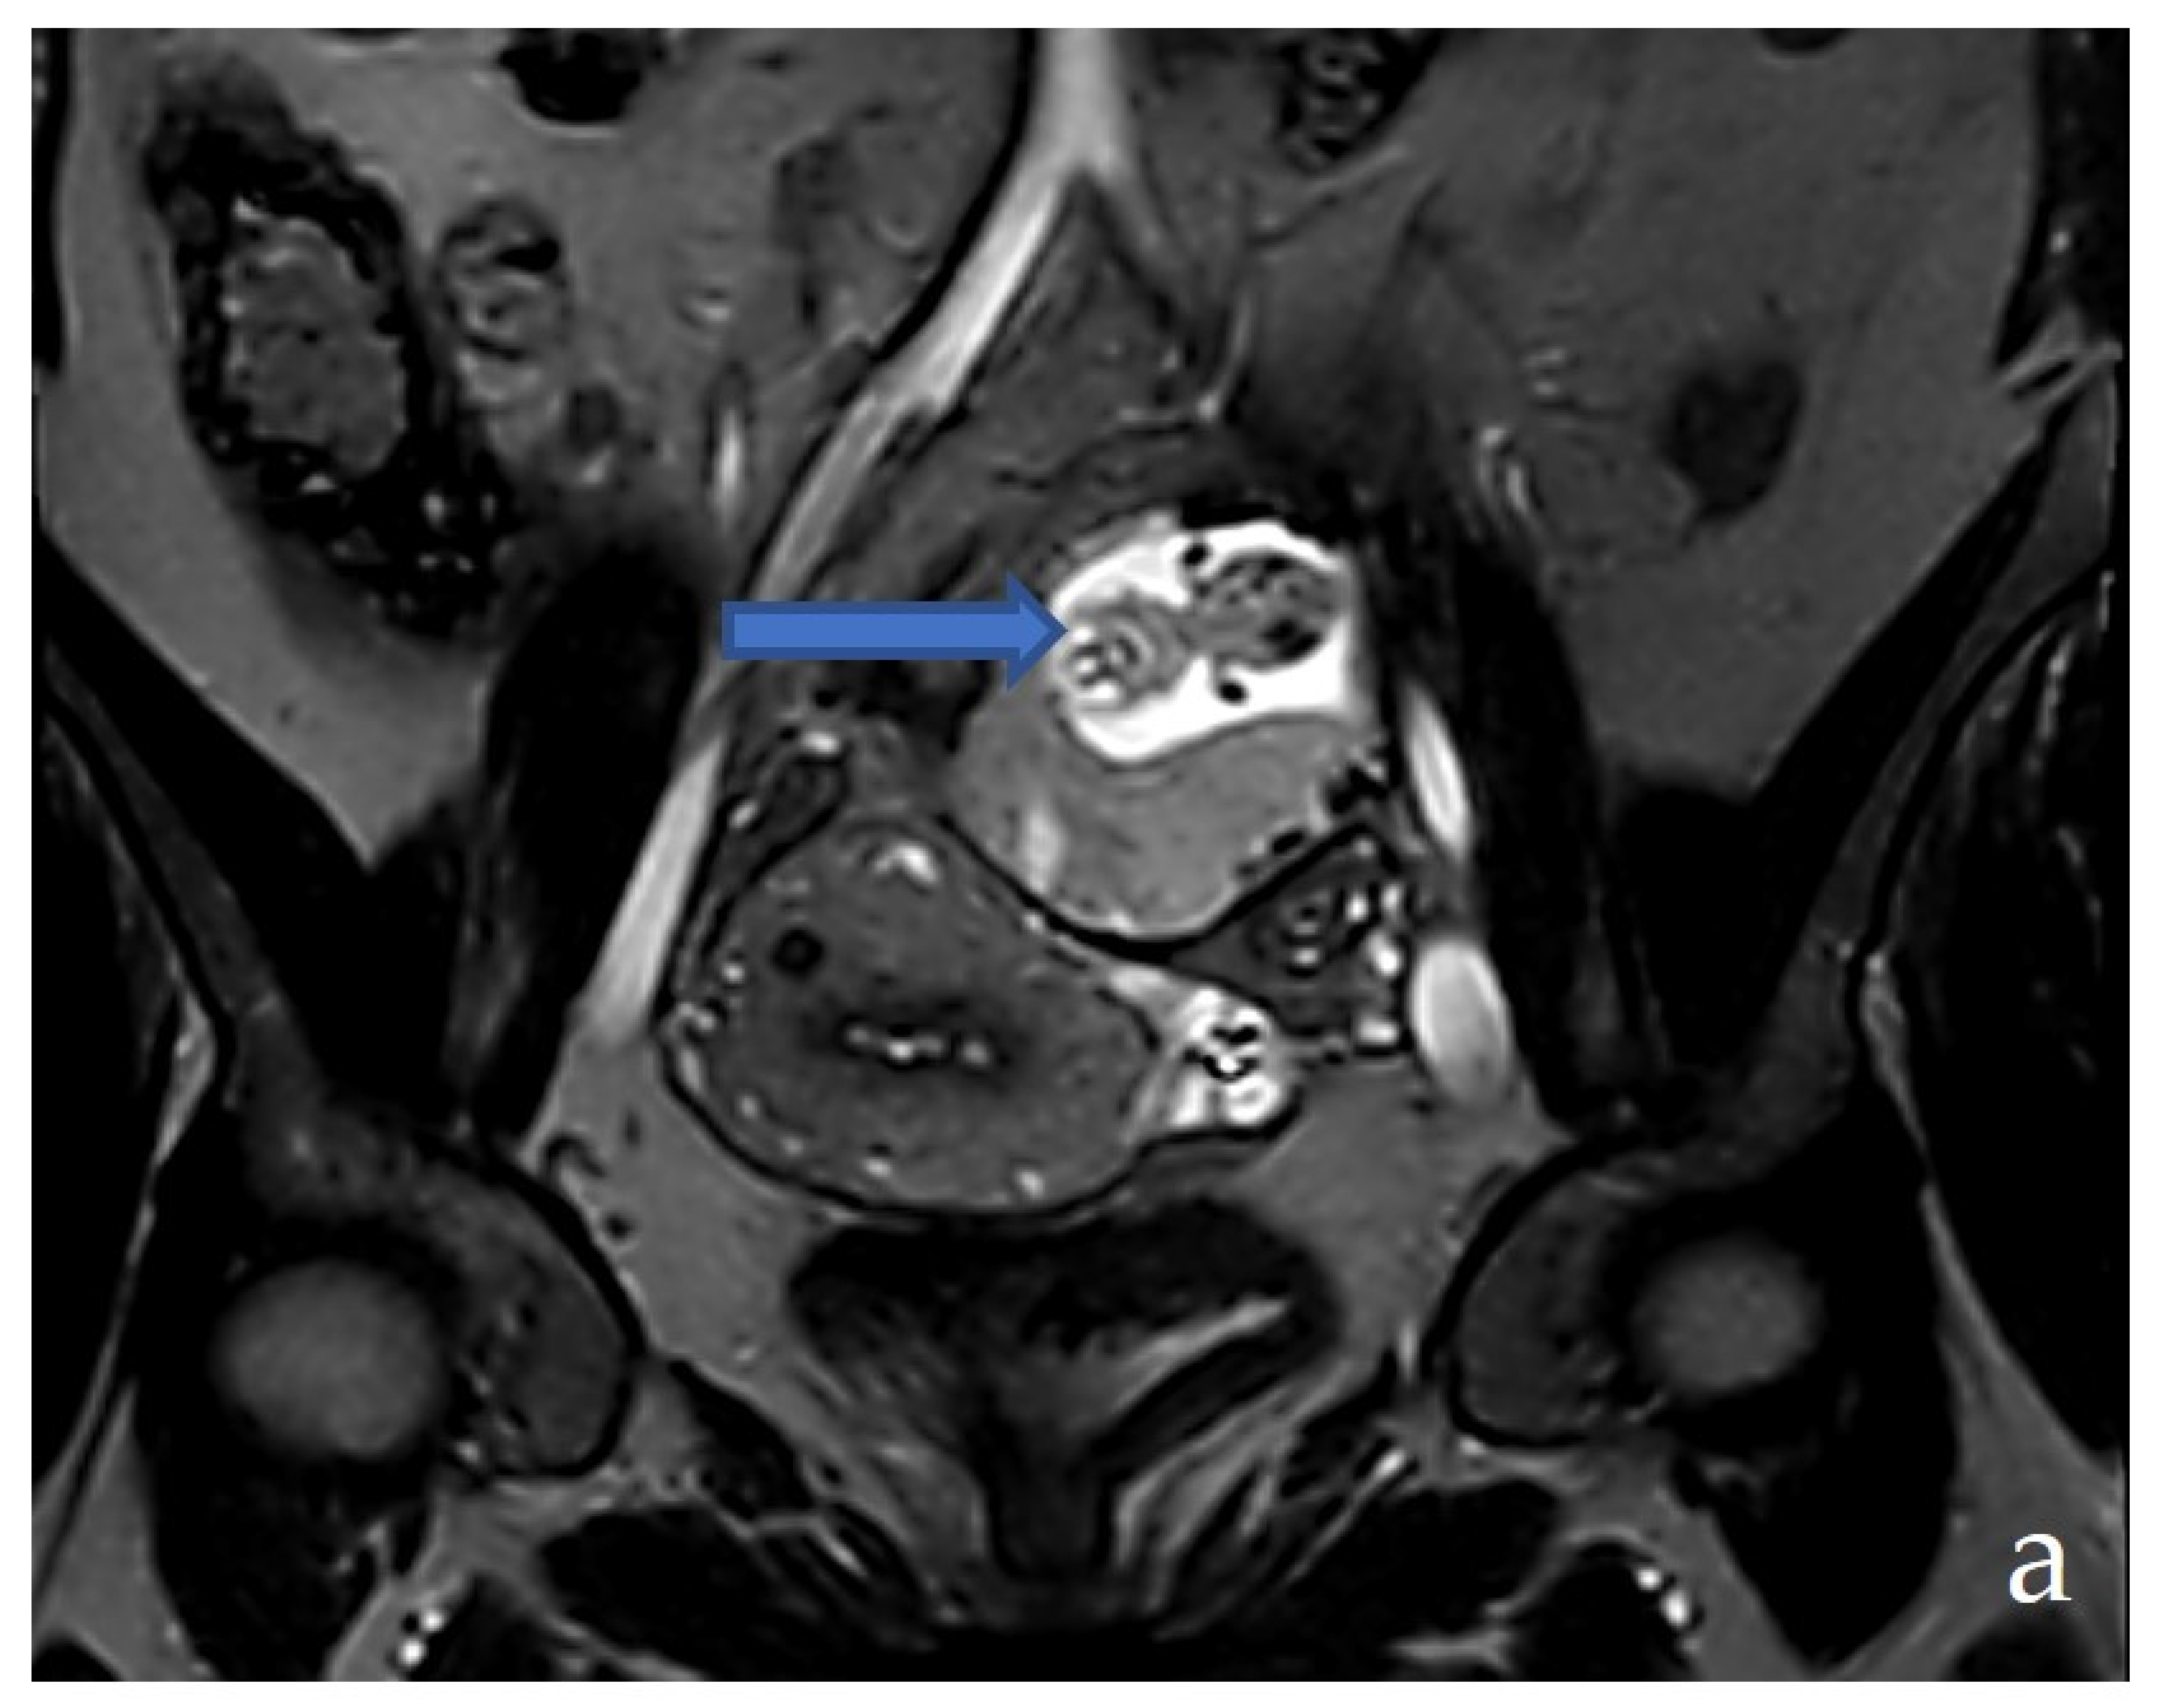

2.3. Diagnostic Assessment and Investigations